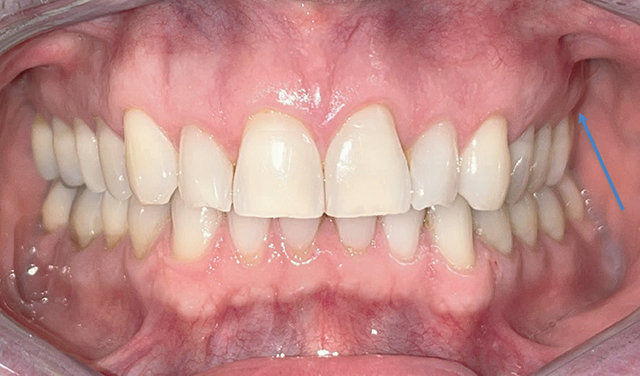

一名 47 岁的男性病史并无异常,因左上磨牙的非典型牙髓疼痛和治疗而转诊。临床和影像学检查发现,这些牙齿周围有一个广泛的、未定义的溶骨区。随后的骨活检诊断为弥漫大 B 细胞淋巴瘤,这是一种高级别非霍奇金淋巴瘤。血液科团队开出了六个周期的化疗处方,并辅以两个周期的甲氨蝶呤。医生应警惕非典型牙痛,考虑进行三维成像检查,以尽早排除恶性病变。教学要点:非典型牙痛应引起医生的警觉,并引导他们进行三维成像检查,以尽早排除恶性病变的诊断。

A 47-year-old male with an unremarkable medical history was referred for atypical endodontic pain and treatment of his left upper molars. Clinical and radiographic examinations revealed an extensive, undefined osteolytic area around these teeth. A subsequent bone biopsy diagnosed diffuse large B-cell lymphoma, a high-grade non-Hodgkin's lymphoma. The hematology team prescribed six cycles of chemotherapy, supplemented by two cycles of methotrexate. Practitioners should be alerted by atypical tooth pain to consider 3D imaging to exclude malignant pathology as early as possible. Teaching point: An atypical tooth pain should alert the practitioner and guide them towards 3D imaging to eliminate diagnostic of malignant pathology as early as possible.